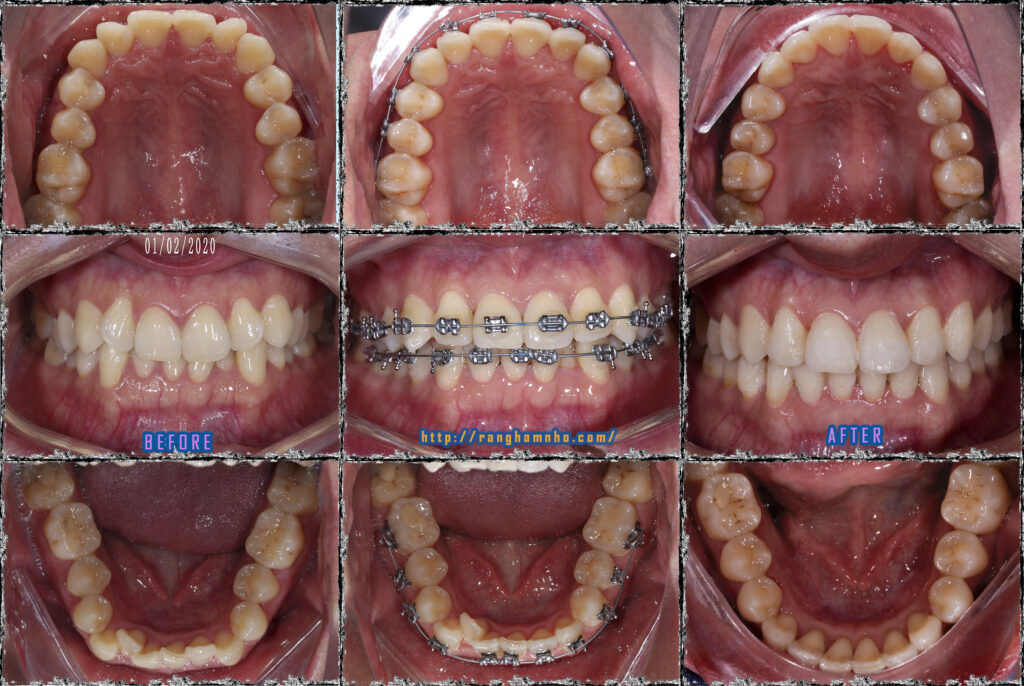

Bệnh nhân có cung hàm vuông, răng chen chúc cả hai hàm, khuôn miệng cười không đẹp. Gắn mắc cài kim loại truyển thống, sử dụng dây cung nong Damon qua các giai đoạn theo trình tự: San bằng, sắp đều, xử lí thiếu khoảng, đóng khớp cắn & tinh chỉnh, tháo niềng.